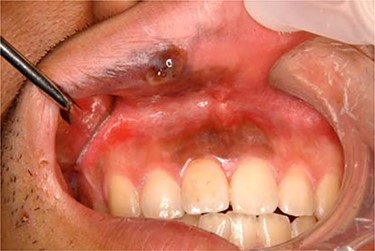

A 20-year-old male patient was referred to our hospital with a small black-colored polyp on the upper lip. On clinical examination, a small polyp measuring 10 × 8 mm in size at the right side of the upper lip mucosa with a brown–black patch expanding from gingivolabial sulcus to the attached gum of incisor tooth was observed (Fig. 1). He was clinically diagnosed with a mucosal malignant melanoma with a metastatic right submaxillary lymph node (Fig. 2). The brown–black patch was melanoma in situ. The polyp was found to be a malignant melanoma following a biopsy. Tumor resection with radical neck dissection was performed 5 days after the biopsy. The tumor excision site was planned, involving some orbicularis oris muscle, including oral mucosa, gingiva and alveolar bone extending from the right canine tooth to the left central incisor tooth (Fig. 3). The defect in the red lip was reconstructed using a musculomucosal flap from the lower lip; simultaneously, the perioral defect was reconstructed using a tongue flap. Initially, the intraoral defect was filled using a tongue flap to the greatest extent possible (Fig. 4). A 10-mm width musculomucosal flap including the right inferior labial artery, in which blood flow had been detected using Doppler ultrasound after right side neck dissection, was designed at the lip mucosa, reaching the left side beyond the center of the lip (Fig. 5). Both the right vermillion border and the shortage of intraoral reconstruction by the tongue flap were repaired using a lip musculomucosal flap (Fig. 6). Both flaps healed well without any congestion or necrosis. They were separated at 2 weeks after primary surgery under deep sedation. The patient could eat and speak without trouble. Nevertheless, cupid’s bow was conspicuous for the gap and the postoperative scar contracted after 3 months. Therefore, correction of the cupid’s bow using Z-plasty of the white lip and reduction of the tongue flap was performed. The secondary operation to correct the misalignment of cupid’s bow and to remove the contraction was successful (Fig. 7).

Intraoral photograph of the initial examination. A small mass measured 10 × 8 mm in size at the right side of the upper lip mucosa with a brown–black patch expanding from gingivolabial sulcus to the attached gum of incisive tooth was observed.